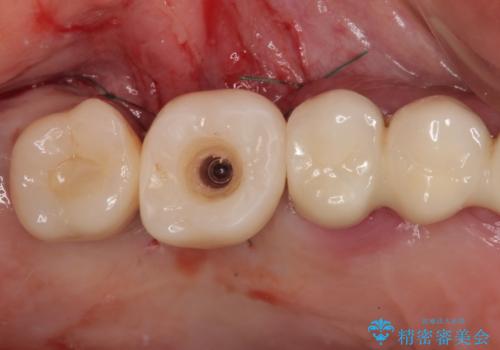

- インプラントが脱落してしまったとのことで来院された患者様です。

歯肉は綺麗に治癒しており、インプラント埋入に十分な骨があったため、速やかにインプラント埋入を行うこととしました。

インプラント埋入の状態が良ければ即日で仮歯を装着し、十分な生着が確認され次第、オールセラミッククラウンにて補綴治療を行うこととしました。